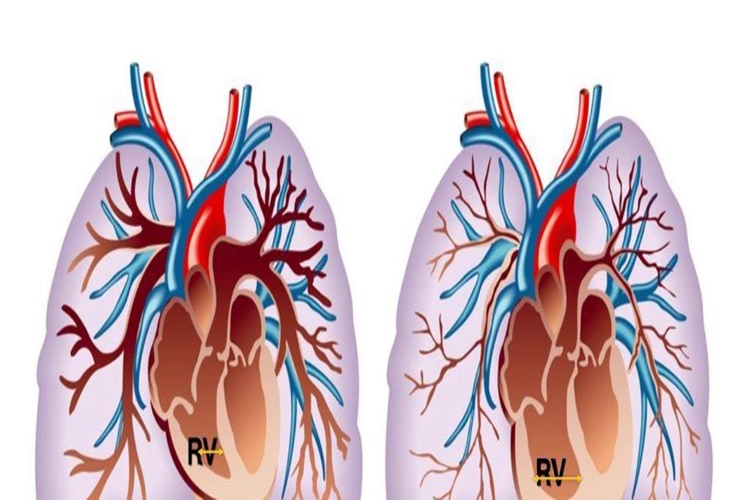

Pnömotoraks Genetik Midir?

Pnömotoraks (pneumothorax),genetik bir hastalık değildir.

Pnömotoraks, akciğerlerin göğüs boşluğundaki hava ile dolduğu veya sızdığı bir

tıbbi durumdur. Genellikle travma, akciğer hastalıkları veya bazı medikal

prosedürler gibi nedenlerle meydana gelir.

Pnömotoraks, spontan pnömotoraks ve travmatik pnömotoraks

olarak iki ana kategoriye ayrılabilir. Spontan pnömotoraks, herhangi bir dış

travma olmaksızın ortaya çıkan ve genellikle akciğerlerdeki küçük bir yırtık

veya lezyon nedeniyle hava kaçağına bağlı olarak gelişen bir durumdur.

Travmatik pnömotoraks ise genellikle bir yaralanma sonucunda meydana gelir ve

genellikle travmatik bir olayın sonucu olarak oluşur.

Pnömotoraksın oluşumunda genetik faktörler, hastalığın başka

bir sebebi olmadığı sürece genellikle büyük bir rol oynamaz. Ancak aile geçmişi

veya genetik yatkınlık bazı sağlık durumlarını etkileyebilir ve bu da

pnömotoraks riskini artırabilir. Bununla birlikte, pnömotoraksın oluşumunda

esas neden, akciğerlere hava kaçağıdır ve genetik faktörler bu tür kaçakların

meydana gelmesine neden olmaz.